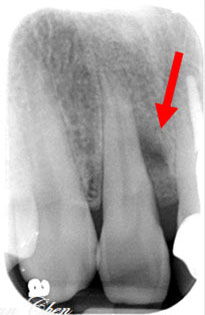

治療前

門牙顎側牙肉反覆腫脹

牙齦紅腫,骨缺損近2/3